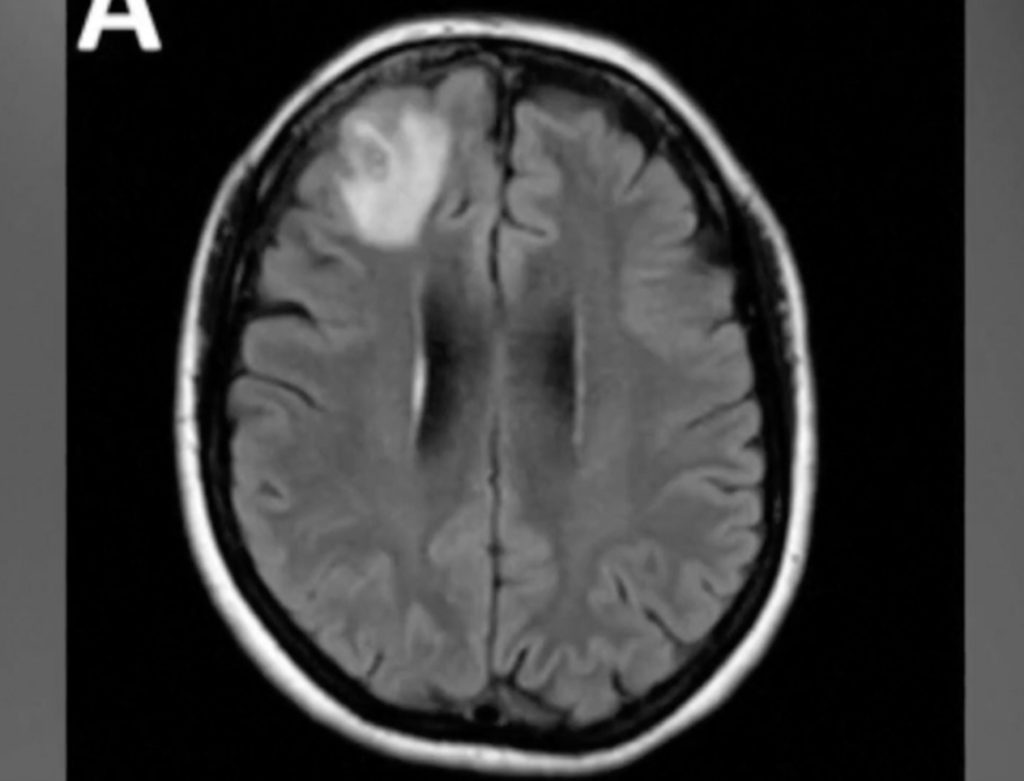

The woman initially sought medical attention due to abdominal pain, diarrhoea, and other symptoms, which gradually escalated to more severe conditions affecting her brain. An MRI scan revealed an anomaly in the right frontal lobe of her brain.